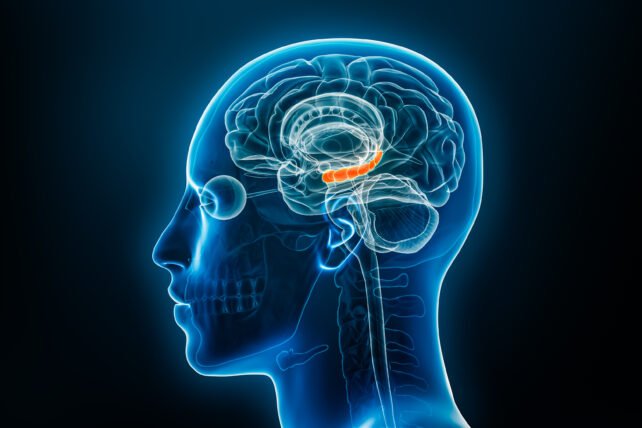

حللت الدراسة، التي شملت بيانات تصوير الدماغ بالرنين المغناطيسي لـ 14,462 مشاركًا من البنك الحيوي البريطاني، أنماط الدماغ لدى مجموعات مختلفة: أشخاص يعانون من ألم مزمن لسبع سنوات على الأقل دون أعراض اكتئاب، وآخرون يعانون من الألم وتطورت لديهم أعراض اكتئاب خلال فترات زمنية محددة. ما كشفت عنه هذه التحليلات كان مفاجئًا: منطقة “الحُصين” في الدماغ، المعروفة بوظائفها الأساسية في التعلم والذاكرة، هي نقطة التحول.

في البداية، وكأن الدماغ يحاول التكيف، أظهر المشاركون الذين عانوا من الألم المزمن دون اكتئاب زيادة طفيفة في حجم الحُصين وتحسنًا في الأداء الإدراكي والذاكرة. هذا يتماشى مع استجابة الدماغ للتعامل مع ضغط الألم. لكن السيناريو يتغير جذريًا مع استمرار الألم. فالأشخاص الذين عانوا من الألم المزمن والاكتئاب على حد سواء أظهروا انخفاضًا في حجم الحُصين وتدهورًا في الأداء الإدراكي، وهي تغييرات تتطور تدريجيًا مع الزمن.

هذا يشير إلى أن الحُصين قد يتكيف في البداية مع الألم المستمر، لكنه يصبح عرضة للخطر تدريجيًا عندما يطول أمد المعاناة. والأهم أن هذه الأنماط المتشابهة لوحظت عبر فئات متعددة من الألم المزمن، مثل آلام الظهر والمعدة والركبة والورك، إضافة إلى الصداع، مما يؤكد أن النتائج لا تقتصر على نوع واحد من الألم.

وتبين أن التلفيف المسنن داخل الحُصين، وهو إحدى المناطق القليلة التي تستمر فيها الخلايا الدماغية الجديدة في التكون خلال مرحلة البلوغ، هو المحور التنظيمي الحاسم ونقطة التحول من الألم المزمن إلى الاكتئاب. في المراحل المبكرة من عملية الألم، أظهرت الخلايا العصبية المولدة حديثًا في التلفيف المسنن نشاطًا متزايدًا، مما يشير إلى أن الدماغ يبني في البداية استجابة وقائية للألم المستمر. لكن بمرور الوقت، تنشط الخلايا المناعية المعروفة باسم “الخلايا الدبقية الصغيرة” (Microglia) بشكل غير طبيعي، مما يعطل الإشارات العصبية الطبيعية في الحُصين. هذا التنشيط غير الطبيعي للخلايا الدبقية الصغيرة يبدو أنه يمثل نقطة التحول التي تبدأ عندها استجابة الدماغ الوقائية الأولية للألم بالفشل.